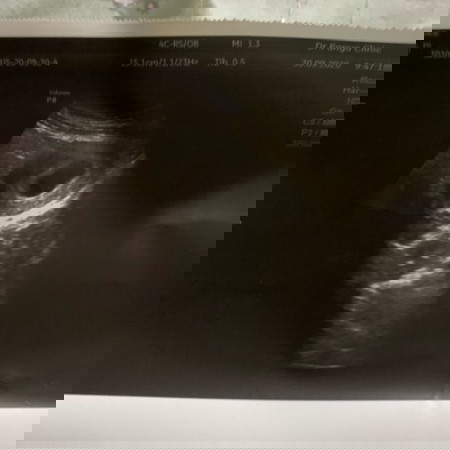

เพิ่งกลับมาจากโรงพยาบาล นอนโรงพยาบาล1คืน เพื่อดูอาการ สาเหตุเลือดออก แล้วคุณหมอห้องฉุกเฉินตรวจภายใน อัลตราซาวด์ บอกว่าปากมดลูกเปิด เลยทำให้เลือดออก แต่น้องปกติดีทุกอย่าง ??? งงแปปนึง ค่ะเราท้องได้4-5เดือนแล้ว ปากมดลูกสามารถเปิดได้หรอค่ะ แล้วมีสิทธิ์ที่จะเปิดอีกมั้ย ??? #กลัวน้องหลุดค่ะ เพราะคุณหมอให้กลับมาพักฟื้นที่บ้าน นอนนิ่งๆอย่างน้อย3วัน โดยไม่ฉีดยา หรือทำอะไรให้เลย